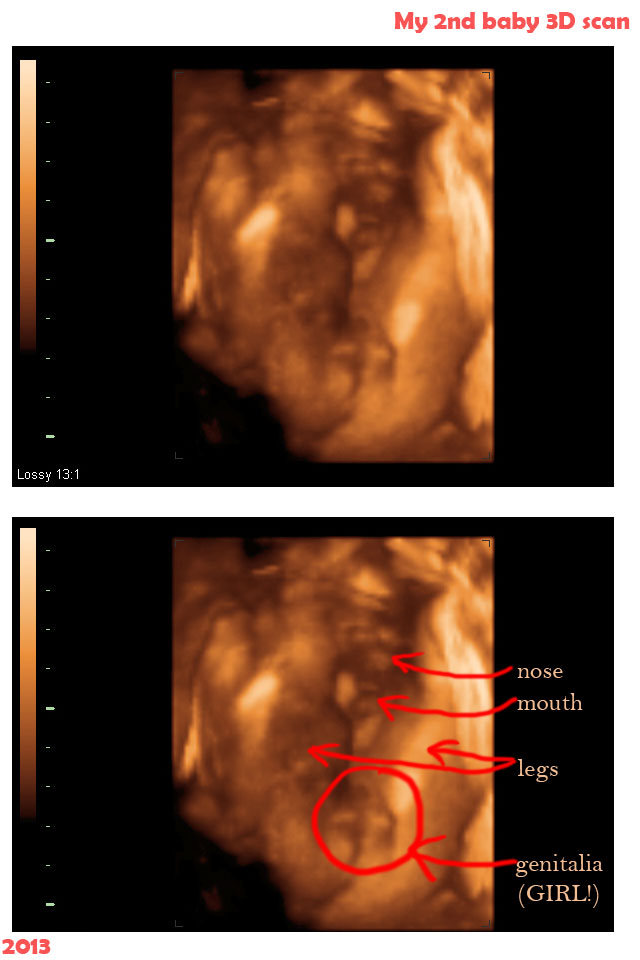

It is at this time that the sonographer will measure the size of your baby check the major organs measure the level of amniotic fluid to make sure that its right and check the position of the placenta. My 4d scan of my 3rd baby was done at baby bond in evesham uk i loved every minute off it and found out im having a little boy x thanks for watching x. A 3d ultrasound takes thousand of pictures or photos of the baby at the once time. People tell us that we have the best 3d ultrasound photo gallery comparing our 3d ultrasound photos with photos after babys birthwe hope you will agree.

I was secretly hoping for a girl since this is our last baby. Moms to be ultrasound was very important during my pregnancy. The ultrasound pictures i have of my boys who are now 9 and 10 are of the old school grainy variety. 3 d imagery was just becoming a thing during my pregnancies and not yet used by my doctor.

It was a very special day for my husband and i. Having a 3d ultrasound is not such a different process to having a 2d ultrasound at least for the mother. Still its helpful to understand the process of your baby boys development so you know what to expect from the photos or just when visualizing the general stages of his growth. Then i had another one at 175 weeks and now they are saying girl.